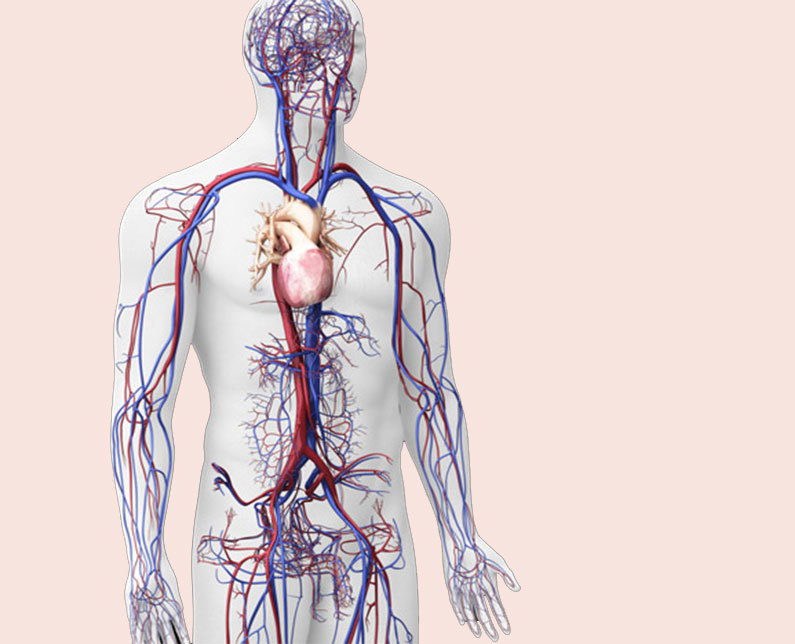

Сердце у человека располагается в грудной полости.

Расположение сердца у человека.

Анатомическое расположение сердца.

Сердце в грудной клетке расположено.

Где расположено сердце у человека анатомия.